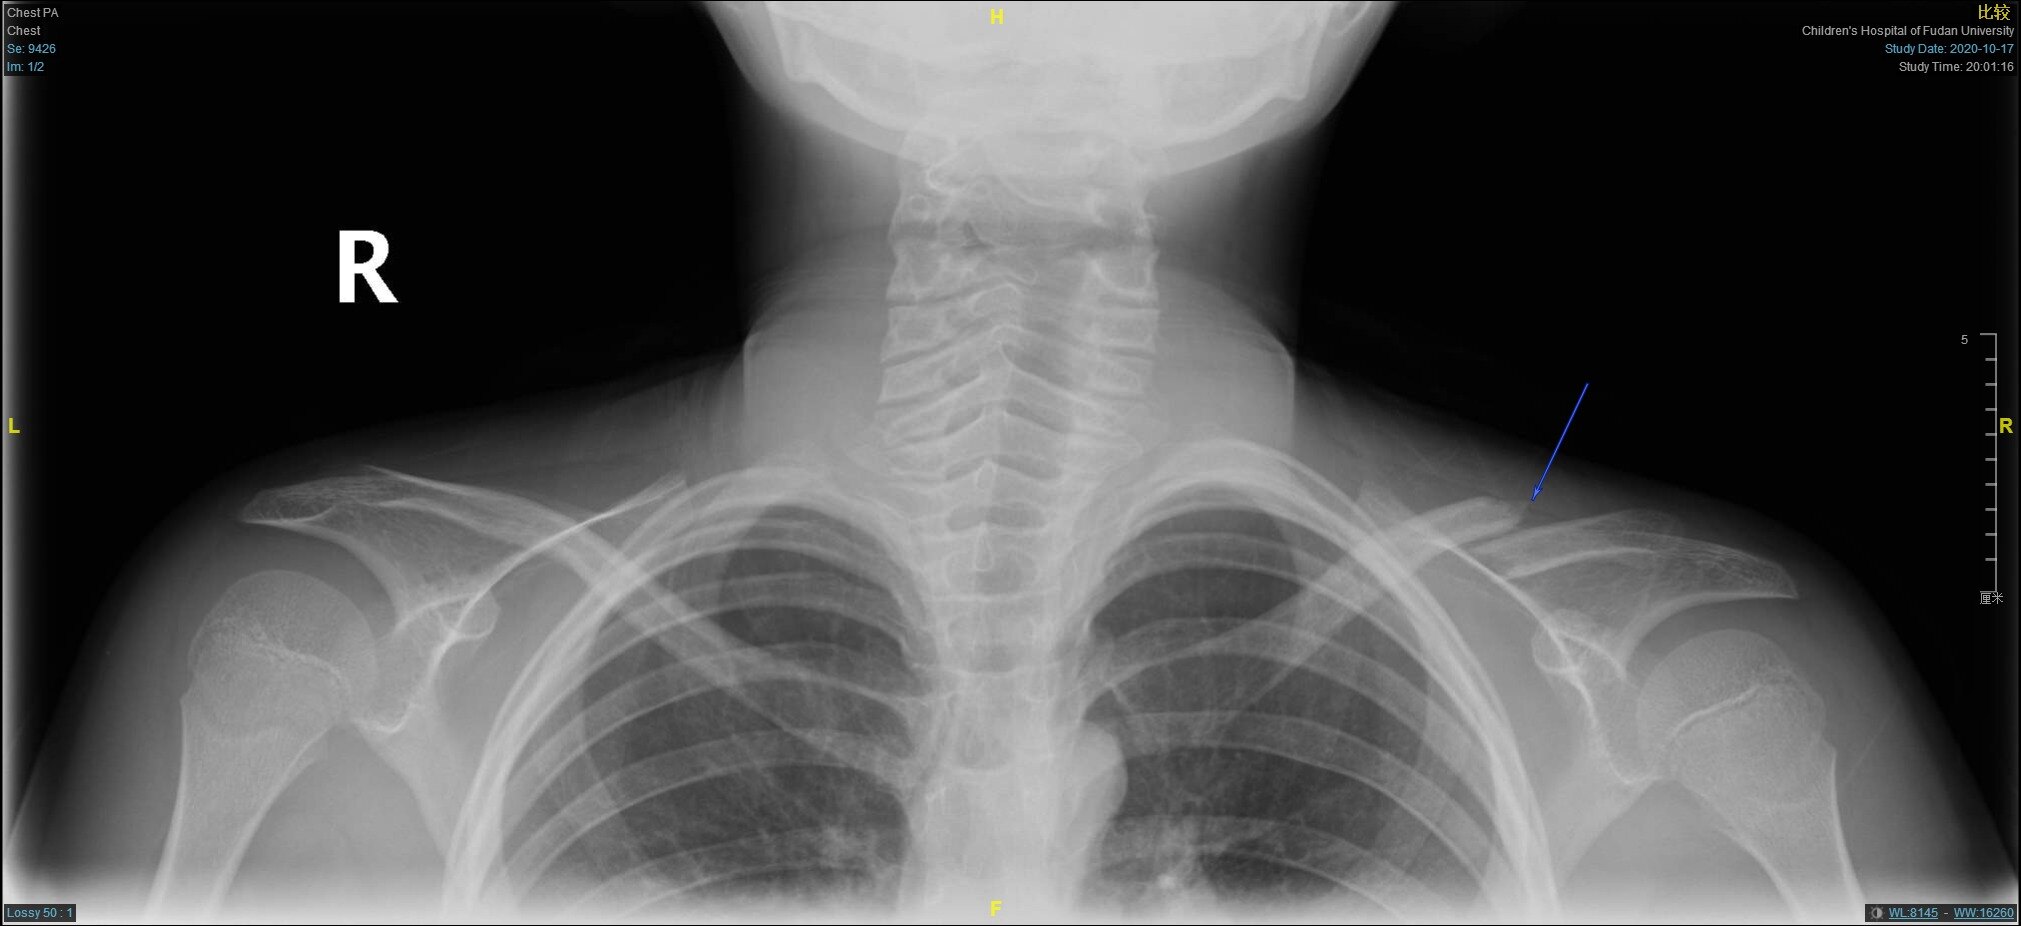

儿童锁骨骨折手术治疗 大于12岁 好大夫在线

儿童锁骨骨折是否合并神经损伤 5 个手势教你简单判断